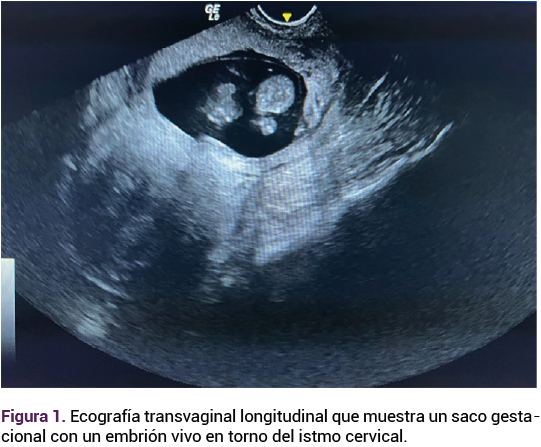

La histerectomía finalizó sin complicaciones inmediatas, con un sangrado estimado de 400 mL y un tiempo quirúrgico de 100 minutos. La pieza quirúrgica se envió a patología (Figura 4), que reiteró el diagnóstico y los hallazgos histopatológicos relacionados con el espectro de acretismo placentario (Figuras 5 y 6). Posterior a la histerectomía la paciente permaneció en observación, con estrecha vigilancia del sangrado. Ante la evolución favorable se le dio el alta del hospital a las 24 horas del posoperatorio.

<strong>Figura 5</strong>

Figura 5.